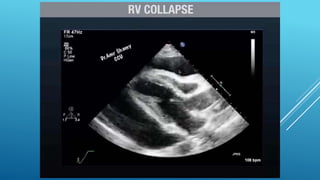

Phases of Hemodynamic changes in Tamponade,

Phases of Hemodynamicchanges in Tamponade, Phase I With Accumulation of pericardial fluid Impairs Relaxation and Filling of Ventricles, Requiring Higher Filling Pressure; during this phase, LV & RV Filling Pressures are Higher than IntraPericardial Pressure Phase II With further Fluid Accumulation, Pericardial Pressure increases Above Ventricular Filling Pressure, Resulting in Reduced Cardiac Output Phase III With further Decrease in Cardiac Output , which is due to Equilibration of :;: Pericardial and (LV) Filling pressures